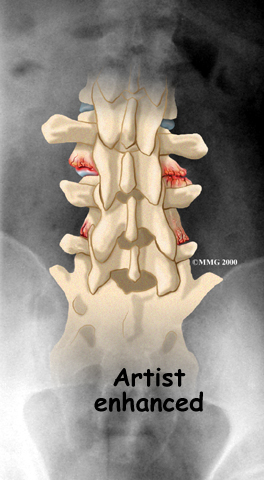

The body responds to this extra pressure by developing bone spurs. As the spurs form around the edges of the facet joints, the joints become enlarged. This is called hypertrophy. Eventually, the joint surfaces become arthritic. When the articular cartilage degenerates, or wears away, the bone underneath is uncovered and rubs against bone. The joint becomes inflamed, swollen, and painful.

Your doctor may order X-rays to reveal if there are problems in the bone tissue in and near the facet joints. The images can show if degeneration has caused the space between the vertebrae to collapse and may show if bone spurs have developed near the facet joints.

Degeneration

A computed tomography (CT) scan may be ordered. This is a detailed X-ray that lets your doctor see slices of bone tissue. The image can show whether the surface of the joint has eroded and whether bone spurs have developed.